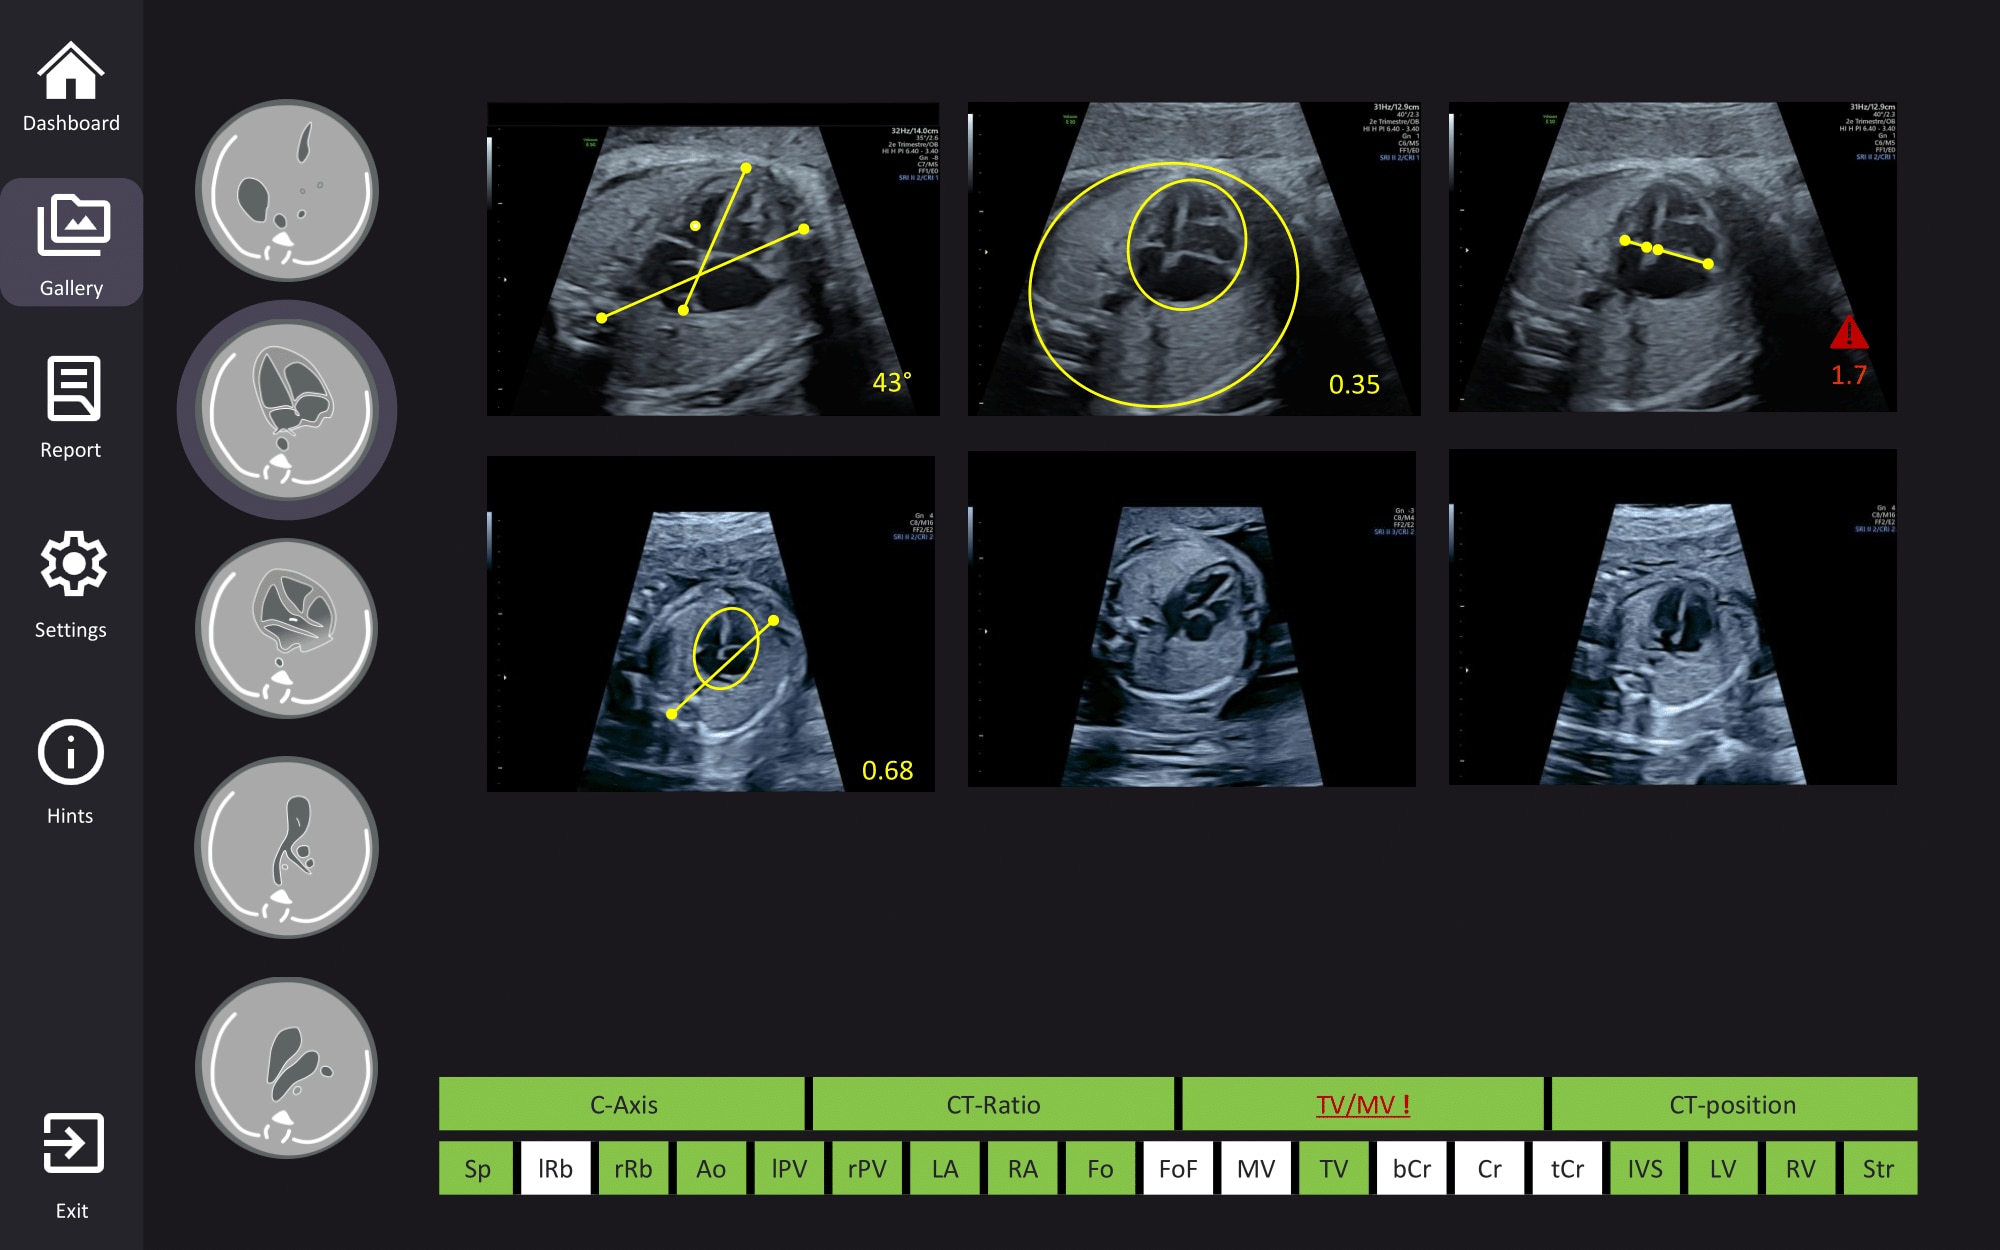

KI‑gestützter Screening‑Assistent für das fetale Herz und Gehirn

Fetoly ist die erste KI‑basierte Echtzeitlösung für den fetalen Ultraschall und unterstützt eine vollständige und standardisierte Untersuchung.

Die Software lässt sich in die meisten Ultraschallsysteme integrieren und liefert sofortiges Feedback zur Steigerung der diagnostischen Sicherheit sowie zur Verbesserung der Schwangerschaftsergebnisse.

• Erkennt sofort über 100 zentrale fetale Strukturen

• Automatisches Einfrieren des Bildes und Auswahl der optimalen Ansicht

• Echtzeit Verhältnismessungen zur Unterstützung bei der Erkennung von Pathologien

• Keine Änderung Ihres bestehenden Workflows erforderlich